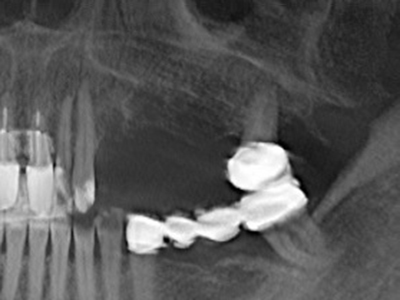

Indikation: Sinuslift

Die Präparation des lateralen Fensters bei der externen Sinusbodenelevation stellt gerade für chirurgisch unerfahrene Implantologen eine große Herausforderung dar. Die knöcherne Bedeckung der Kieferhöhle ohne eine Verletzung der darunterliegenden Schneider’schen Membran abzutragen ist dabei nur ein Teil der Operation – nach Schaffung eines ausreichenden Zugangs muss die Kieferhöhlenschleimhaut vorsichtig mobilisiert werden, um Raum für das einzubringende Material bzw. die Implantate zu schaffen. In dieser Indikation ist die Piezochirurgie zweierlei hilfreich: zum einen kann durch Verwendung diamantierter Instrumente eine selektive Knochenabtragung erfolgen und die darunter liegende Schleimhaut bleibt bei vorsichtiger Vorgehensweise intakt. Zum anderen unterstützen die Ultraschallfrequenzen zusätzlich eine komplikationslose Ablösung der Schleimhaut – sie werden durch spezielle stumpfe Ansätze in den Spaltraum zwischen Schleimhaut und Kieferhöhlenboden übertragen (Cassetta, Ricci et al. 2012, Pereira, Gealh et al. 2014) (Rickert, Vissink et al. 2013). So erscheint es nicht verwunderlich, dass in aktuellen Übersichtsarbeiten über die externe Sinusbodenelevation neben der Verwendung von rauen Implantatoberflächen und dem Einsatz von Knochenersatzmaterialien auch der Einsatz von piezoelektronischen Geräten als positiv bewertet wird (Wallace, Tarnow et al. 2012).